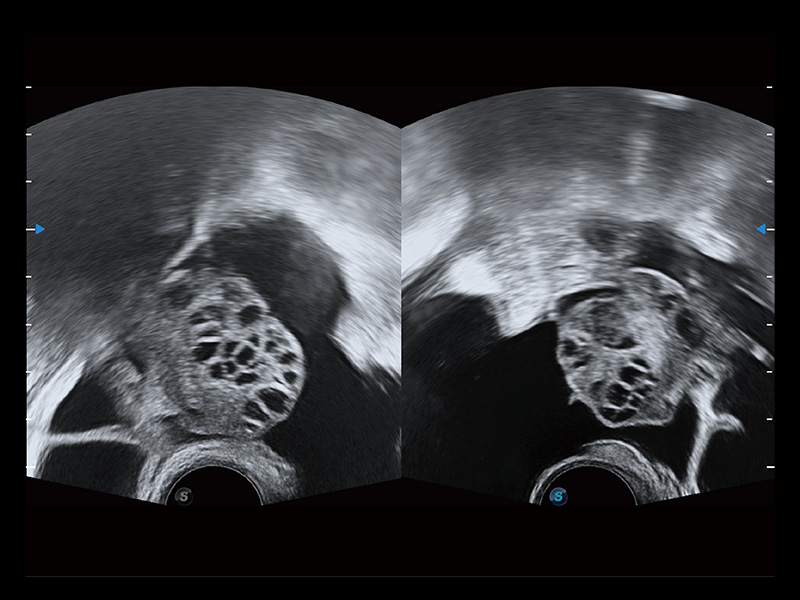

超声引导下双侧卵巢穿刺取卵

卵巢多囊样改变